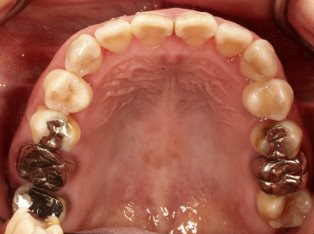

乱ぐい歯、でこぼこがとても酷い状態になります。歯が前後的に重なってしまっている、八重歯になっているなどがこのジャンルに入ります。

顎の大きさと歯の大きさのギャップが大きく、時には歯を抜かないと矯正治療ができない場合もあります。当院では治療期間が長くなるが抜かない治療方針など、一つの治療プランだけでなく、さまざまな可能性の治療方針を説明させて頂くよう心掛けております。こういった考え方はインフォームド・チョイスと言われ近年大切にされている考え方と言われております。

治療前

治療終了前